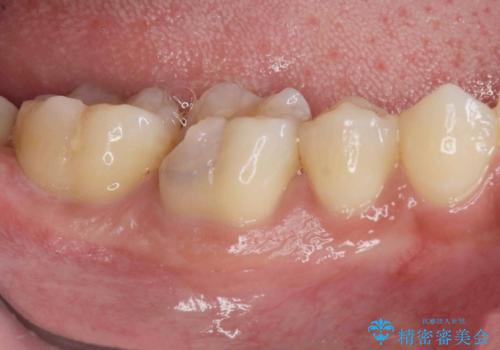

3. 放置してしまった虫歯の治療の治療後